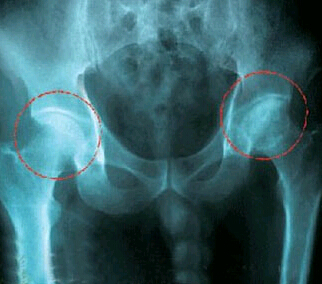

7年前,刘奶奶就隐约感觉到左侧髋关节疼痛,但是由于疼痛不明显,老人也不想麻烦自己的儿女,病发后她便卧床休息,抗几天病情就有些缓解。但是近两年,不仅疼痛加剧,而且逐渐出现左侧跛行。老人日益严重的病情引起了儿女的注意,他们带老人去医院检查,确诊为“左髋关节骨性关节炎”,考虑到老人年事已高,手术风险高,医院建议她保守治疗,可是远水解不了近火,保守治疗好几个月也不见疗效,疼痛一直在继续。

几经辗转,刘奶奶最终来到莱矿医院,接诊的是我们医院的骨外科主任张连双,张主任仔细查看了她的病情,诊断为左髋关节退行性骨关节炎,股骨头坏死,不接受治疗会严重影响日后生活。刘奶奶告诉张主任,因为疼痛难忍,自己甚至有过要自杀的念头,自己宁死也不想下半辈子瘫痪在床,更不想拖累子女。

考虑到髋关节置换手术风险较高,张主任召集科室人员,为老人研究手术方案,同时提前预设手术中可能发生的突发状况,以确保万无一失。手术中,医生将老人下身麻醉,将左侧坏死的股骨头切除并安装上人工股骨头。手术后仅半个月,老人就能在家人的搀扶下下地走动了。双脚沾地的那一刻,老人流下了激动地泪水:“半年了,一直在床上躺着,我都不晓得怎么走路了,现在终于能“脚踏实地”了,疼痛也好多了。